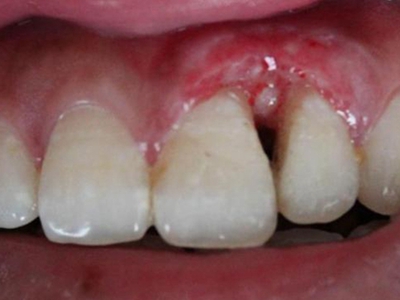

肿块有的有蒂,如息肉状;有的无蒂,基底宽广,生长较慢,但在女性妊娠期间可能迅速增大。较大的肿块可以遮盖一部分牙及牙槽突,表面可见牙压痕,易被咬伤而发生溃疡,伴发感染。随着肿块的增长,牙槽骨壁逐渐被破坏,牙可能发生松动、移位。

局部刺激因素,包括菌斑、牙石、食物嵌塞或不良修复体的刺激,引起局部长期慢性炎症,致使牙龈结缔组织形成反应性增生物,即牙龈瘤。此外,牙龈瘤可能和内分泌有关,妇女怀孕期间容易发生牙龈瘤,而分娩后会缩小或停止生长。

对于牙龈瘤可在局麻下手术切除,切除必须彻底,否则易复发。如果复发,仍可手术切除。多次复发者,即使病变波及的牙无松动,也应将牙拔除,防止再发。